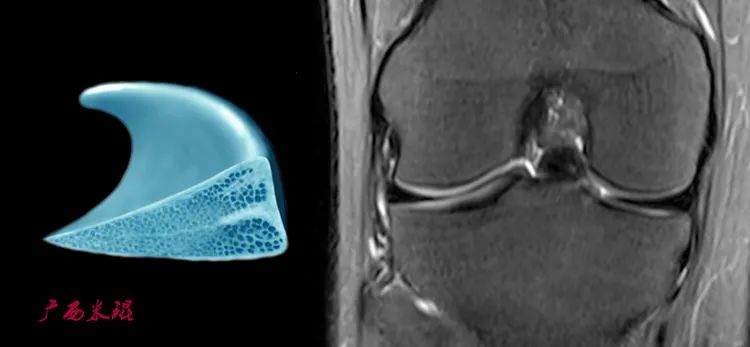

二、了解正常半月板的MRI表现

1、信号

正常半月板由于含有I型胶原组织,因此不管MRI如何扫描,所有序列半月板成像都呈现均匀的低信号。

2、形态

半月板为外周较厚、内侧菲薄的半月形结构,因此,根据MRI切面不同半月板的成像表现为类矩形、蝴蝶结形、三角形,刚开始学习的时候可能感觉很难,但无论如何也要把解剖形态与MRI表现联系起来。